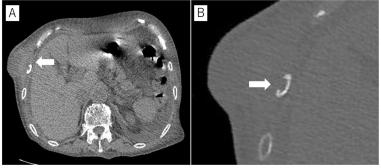

实验室检查显示白细胞计数为7200/μL,C反应蛋白水平为5.03 mg/dL。计算机断层扫描(CT)显示约65 × 30 mm的肿块(图1a)伴有溶骨性改变,累及右侧第8肋(图1b),而没有明显的胸内肺部病变。根据快速生长率和CT表现,强烈怀疑为恶性胸壁肿瘤。因此,通过第8肋整块切除肿瘤。从宏观上看,标本为一个灰白的固体块,大小为7.5 ×5.5 ××4.0厘米。切取标本时,排出大量粘稠脓液。显微镜下,标本表现为坏死灶和非干酪样上皮样细胞肉芽肿伴多核巨细胞(图2a)。肉芽肿性病变延伸至肋骨,浸润骨皮质(图2b)。脓涂片的Ziehl-Neelsen染色显示抗酸杆菌的存在,其培养显示鸟分枝杆菌的生长。最后确诊为第8肋鸟分枝杆菌脓肿。术后,由于患者年龄大,病变解剖切除完整,未接受任何抗生素治疗,术后第12天顺利出院。出院后1个月的随访中,无感染迹象及其他与手术相关的不良事件。

图1. 计算机断层扫描。A:胸壁肿块,约65 × 30 mm。B:右第8肋有溶骨性改变。